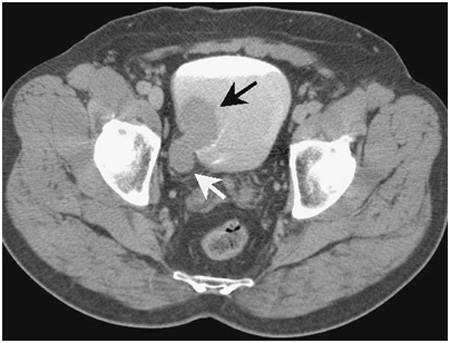

- КТ и МРТ используются для оценки состояния органов малого таза, особенно при прорастании опухоли в мышечный слой. Эти методы наиболее информативны при местном распространении опухоли и для определения состояния регионарных лимфатических узлов и верхних отделов мочевыделительной системы.

- УЗИ мочевого пузыря, компьютерная томография и МРТ. Эти методы визуализируют патологическое новообразование и позволяют оценить его размеры и распространенность.

Компьютерная или магнитно-резонансная томография. Эти методы позволяют получить снимки мочевых путей.